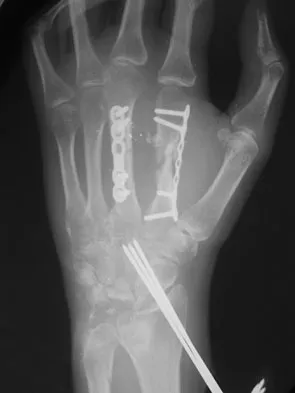

A patient with rheumatoid arthritis with both ankle and subtalar involvement was treated as shown in Figures 11a and 11b. What complication is unique to this type of fixation?

Explanation

The interlocking screws at the proximal end of the rod can act as a stress riser and lead to fracture. Postoperative pain at this level should prompt inclusion of this diagnosis in the differential. Removing the screws following bone union can decrease the chances of this occurring. A short rod that avoids the diaphyseal area may also be beneficial. Rotatory deformity is controlled by the perpendicularly oriented distal transfixion screws. Talar osteonecrosis would be unusual since the dissection can be minimized with an intramedullary rod. Any type of hardware can fail if the construct does not lead to a solid arthrodesis. Nunley JA, Pfeffer GB, Sanders RW, et al (eds): Advanced Reconstruction: Foot and Ankle. Rosemont, IL, American Academy of Orthopaedic Surgeons, 2004, pp 236-237. Thordarson DB, Chang D: Stress fractures and tibial cortical hypertrophy after tibiotalocalcaneal arthrodesis with an intramedullary nail. Foot Ankle Int 1999;20:497-500.